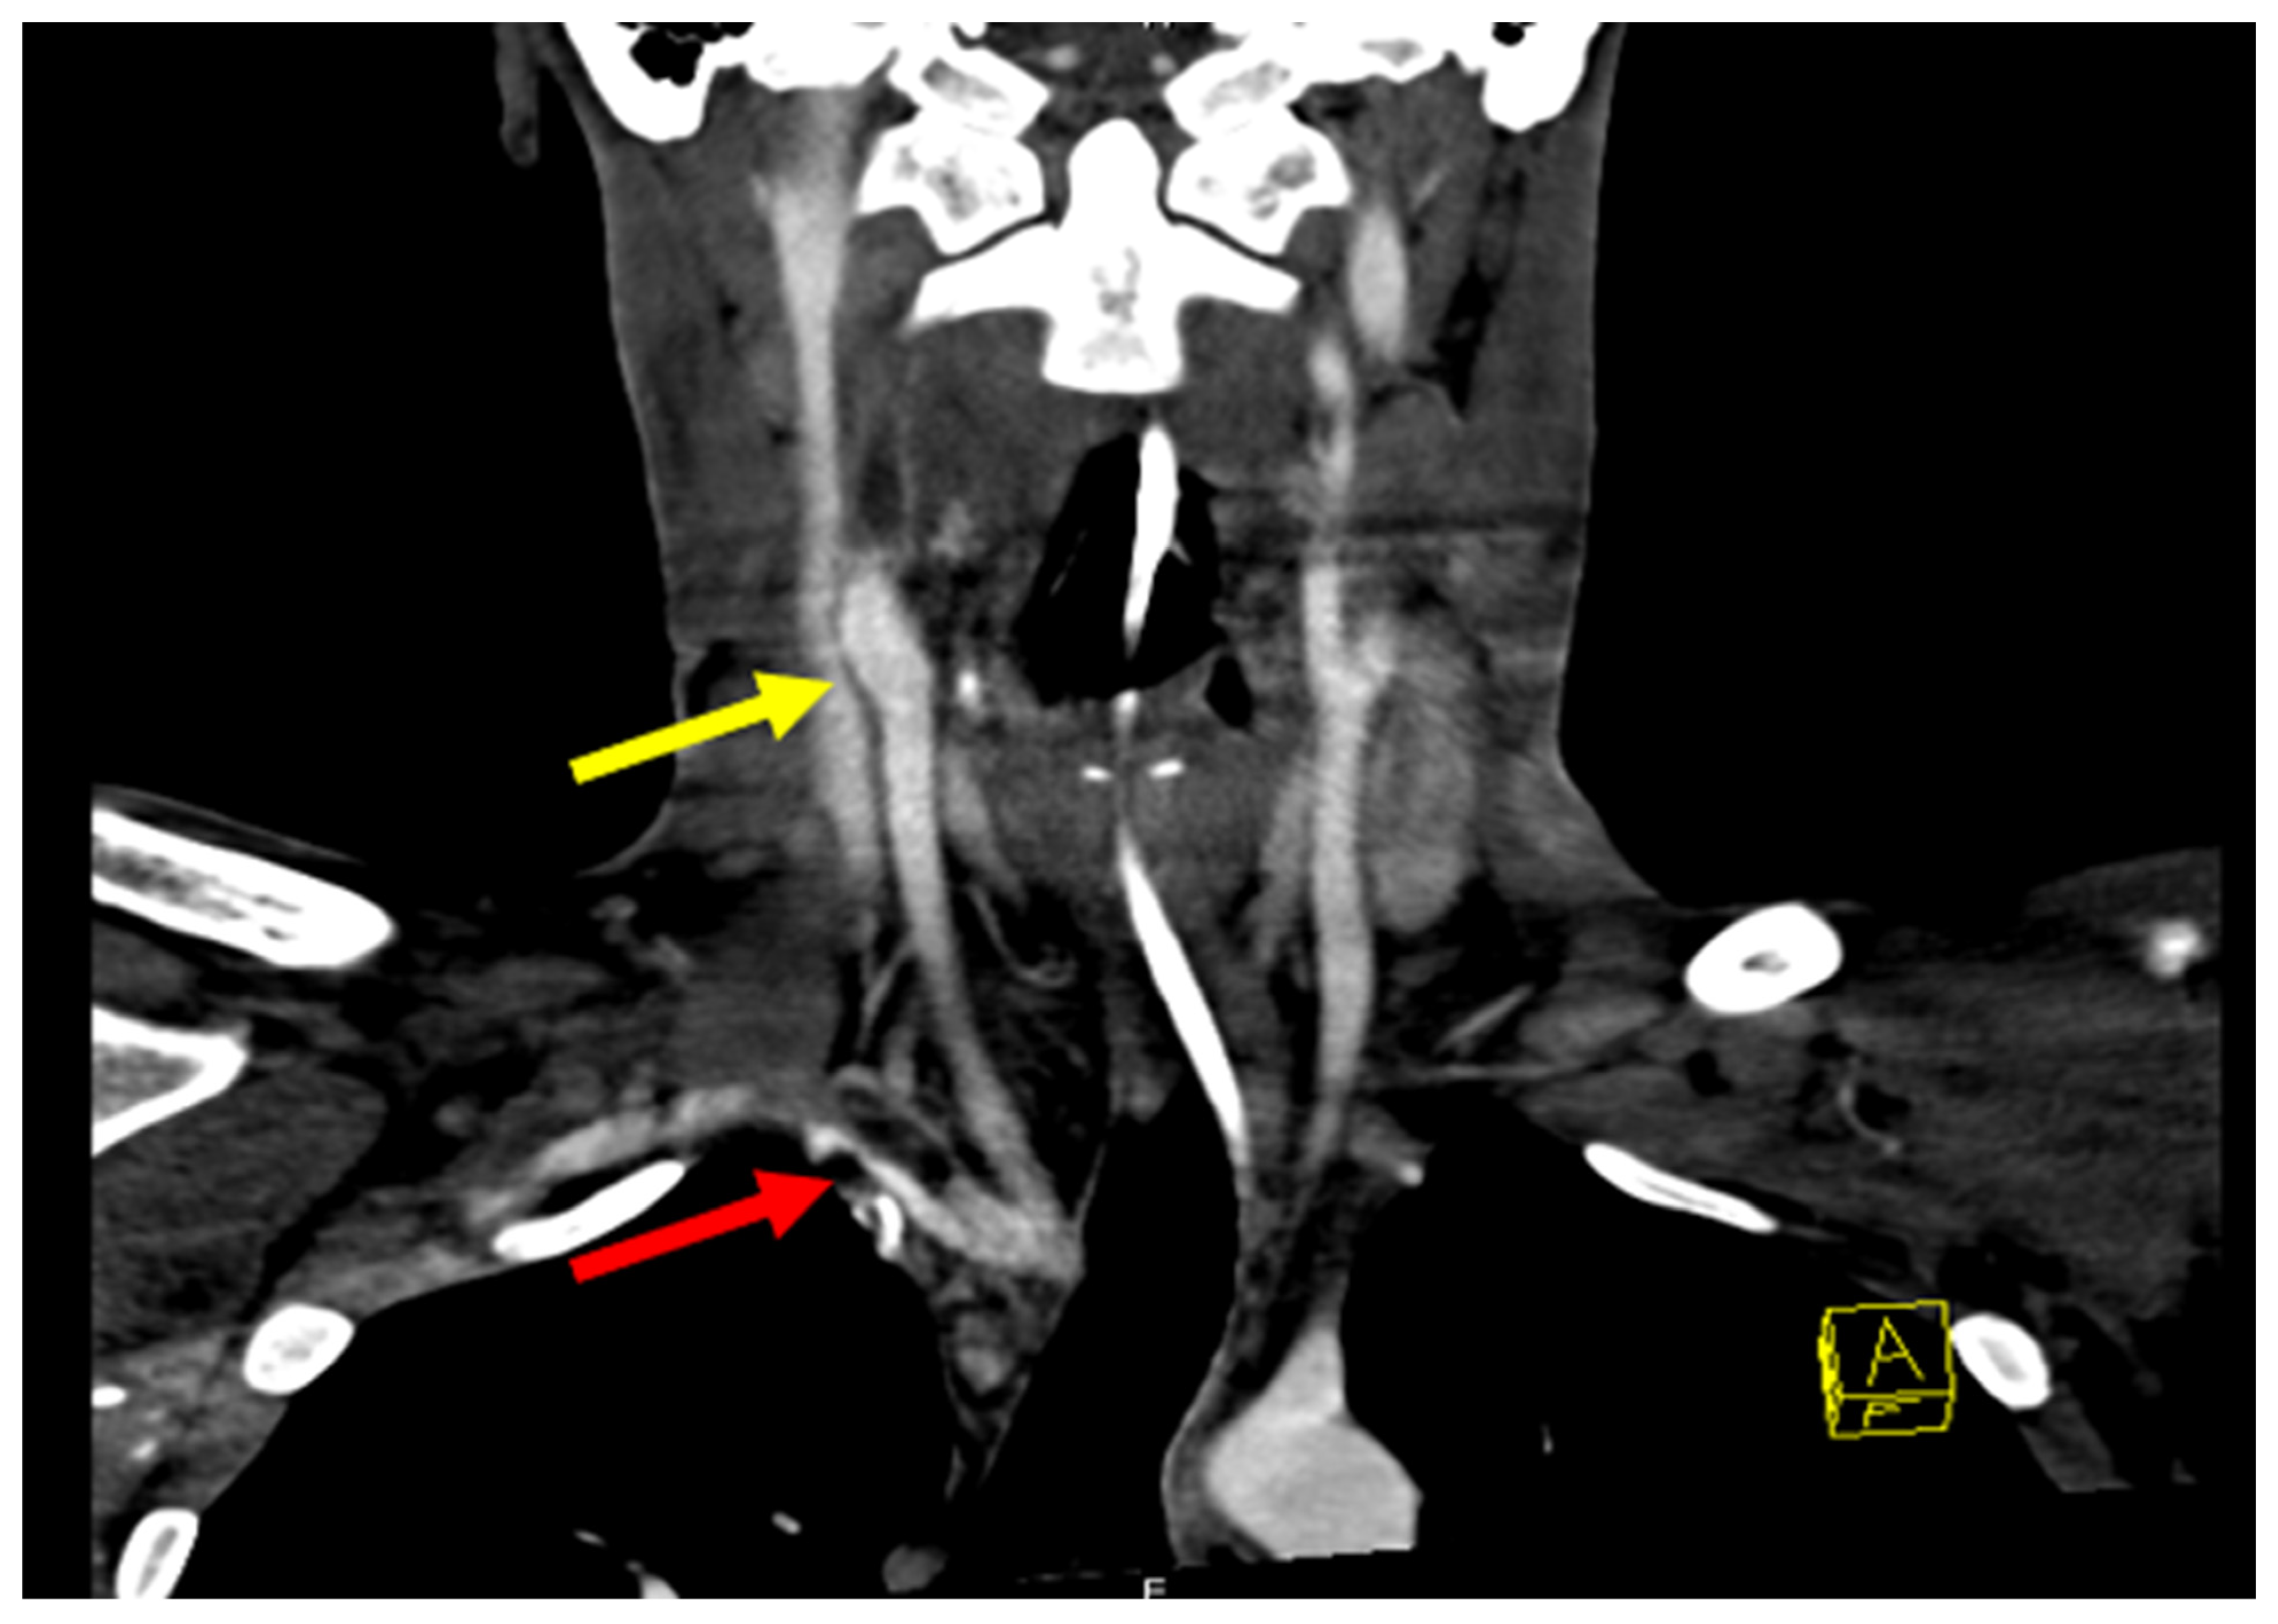

The patient soon developed fever and leukocytosis which prompted readmission for infectious workup. Repeat CT angiograms showed a pseudoaneurysm of the right brachiocephalic artery with evidence of active bleeding and associated anterior mediastinal hematoma. Additional findings included a rim-enhancing fluid collection containing a small focus of gas anterior to the sternum as well as the presence of thrombi in the right brachiocephalic artery, subclavian artery, and common carotid artery (Figure 3).

Figure 3. Angiography revealing pseudoaneurysm of right IC and thrombus (yellow arrow). Occluded right internal carotid from the bifurcation at the neck to the skull base and possibly further. Narrowing at the origin of the right vertebral artery from nearly occlusive thrombus in the right subclavian artery. A large pseudoaneurysm of the right brachiocephalic artery is also visible (red arrow).